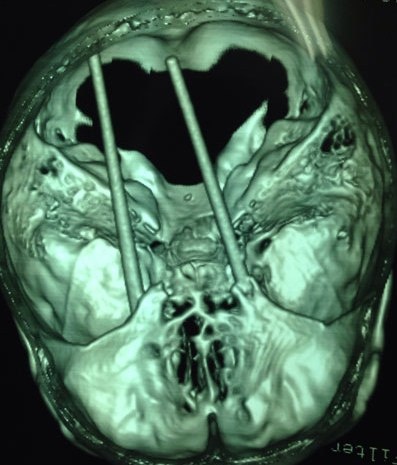

| Đôi đũa đâm qua hốc mắt xuyên lên sàn não bệnh nhân. |

TS.BS Nguyễn Kim Chung, Phó khoa Ngoại thần kinh của bệnh viện Chợ Rẫy, cho biết bệnh nhân bị vết thương ở 2 hốc mắt, dị vật xuyên mắt, xuyên mô não. Các bác sĩ đã mở sọ lấy ra đôi đũa gãy nằm trong não. “Ê-kíp bác sĩ của khoa Ngoại thần kinh phối hợp với khoa Mắt phẫu thuật trong suốt 4 giờ liền”, bác sĩ Chung cho biết.